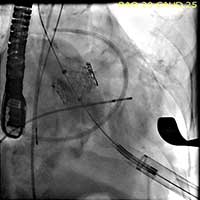

- After deployment, both TEE and another angiographic root injection are performed to confirm the position of the valve (Figure 7, 8), rule out paravalvular or central leak and to confirm the patency of the coronary arteries. Occasionally, the valve may require an additional insufflation with additional saline.